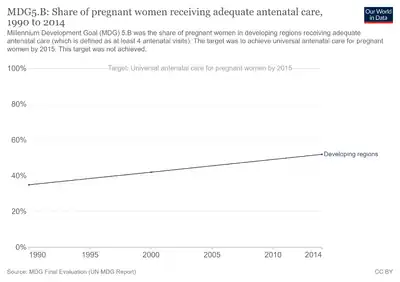

Prenatal care improves pregnancy outcomes.[9] Prenatal care may include taking extra folic acid, avoiding drugs, tobacco smoking, and alcohol, taking regular exercise, having blood tests, and regular physical examinations.[9] Complications of pregnancy may include disorders of high blood pressure, gestational diabetes, iron-deficiency anemia, and severe nausea and vomiting.[3] In the ideal childbirth labor begins on its own when a woman is "at term".[14] Babies born before 37 weeks are "preterm" and at higher risk of health problems such as cerebral palsy.[4] Babies born between weeks 37 and 39 are considered "early term" while those born between weeks 39 and 41 are considered "full term".[4] Babies born between weeks 41 and 42 weeks are considered "late term" while after 42 week they are considered "post term".[4] Delivery before 39 weeks by labor induction or caesarean section is not recommended unless required for other medical reasons.[15]

Prenatal medical care is the medical and nursing care recommended for women during pregnancy, time intervals and exact goals of each visit differ by country.[76] Women who are high risk have better outcomes if they are seen regularly and frequently by a medical professional than women who are low risk.[77] A woman can be labeled as high risk for different reasons including previous complications in pregnancy, complications in the current pregnancy, current medical diseases, or social issues.[78][79]